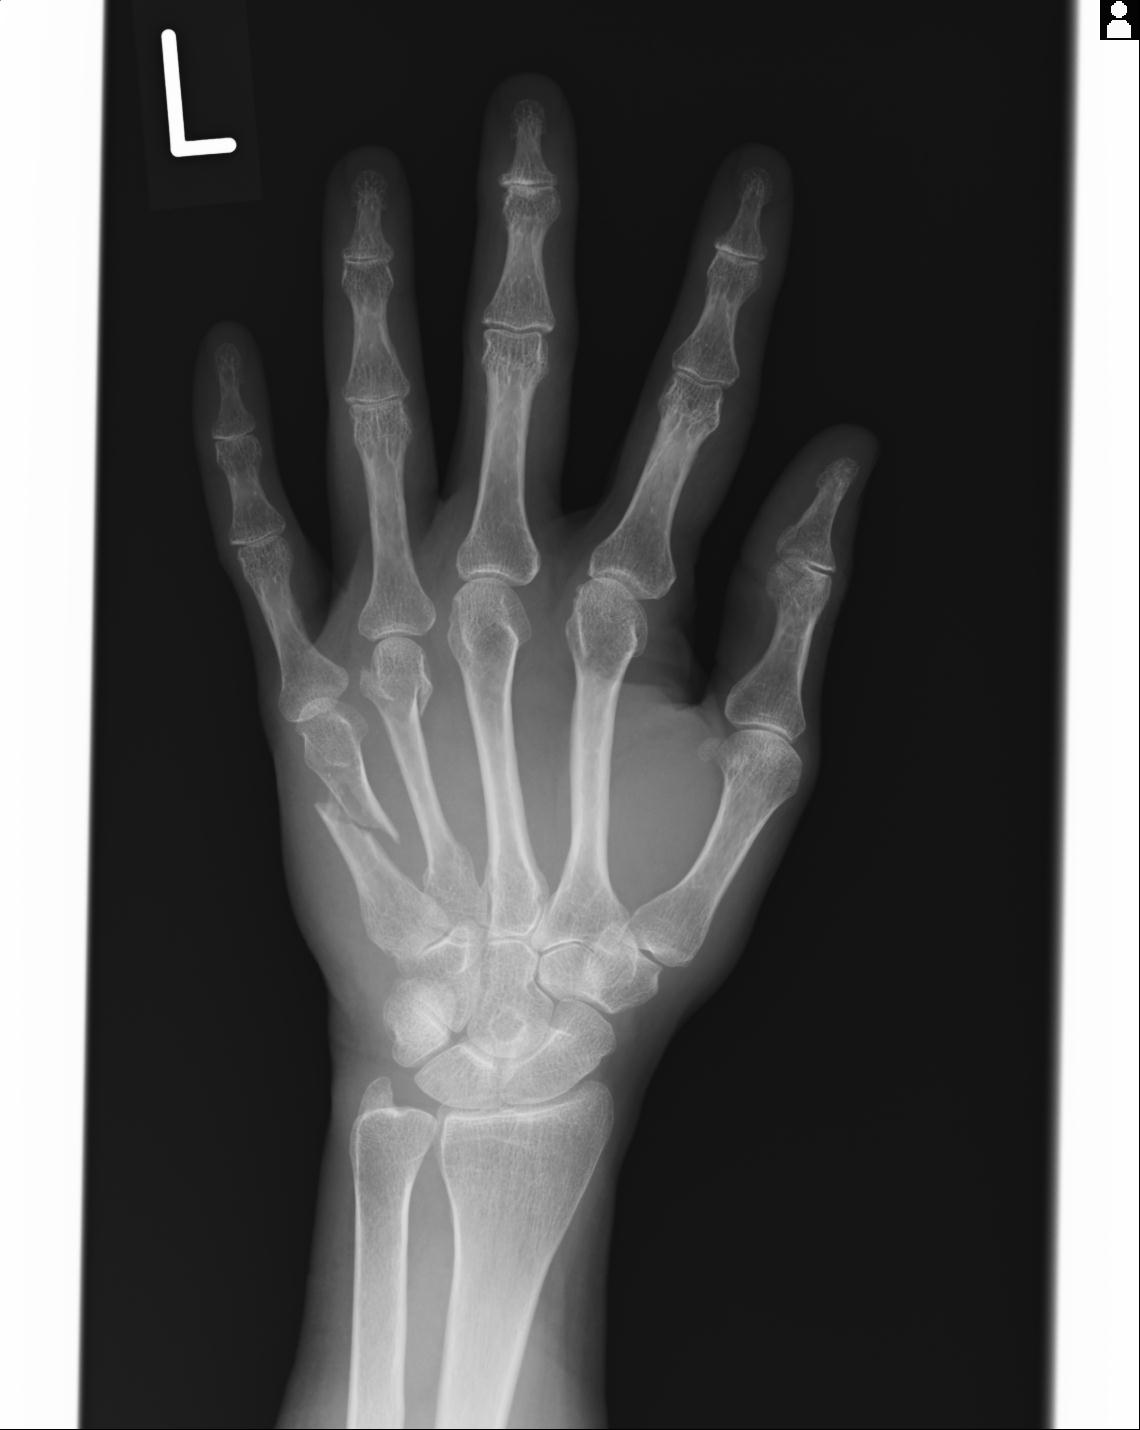

46666 1/23 両股正面+軸と右手関節 2R 76歳女性 右橈骨遠位端

46666 1/28 両股正面+軸と 1/26 右手関節 2R 76歳女性 右転子部骨折